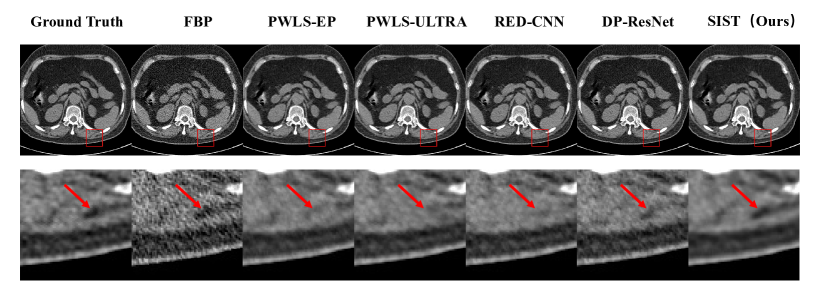

Refer to caption

Figure 8: Visual results of 5% dose in Simulated Dataset. The first row is denoised images. The second row is zoomed regions in red boxes. All images displayed are from the same window of [-160, 240].

4.3.2 Simulated Dataset

To further evaluate the performance of the proposed method on different dose levels, we generate the projection data and insert noise follow [39]. We evaluate the performance on three dose levels: 20%, 10%, and 5%. The quantitative results are shown in Tab.2. From the table, we can observe that our methods achieve the best results in all dose levels: 20%, 10%, and 5%. Same as the LDCT dataset, the deep learning methods show superior performance that iterative reconstruction methods. Moreover, our method still has great performance at the very low dose situation (5% dose), which even over the path the second method in 10% dose. Fig.6, Fig.7, and Fig.8 show the visual results for dose levels 20%, 10%, and 5%. From these visual results, we can observe that our method can preserve more details while denoising.